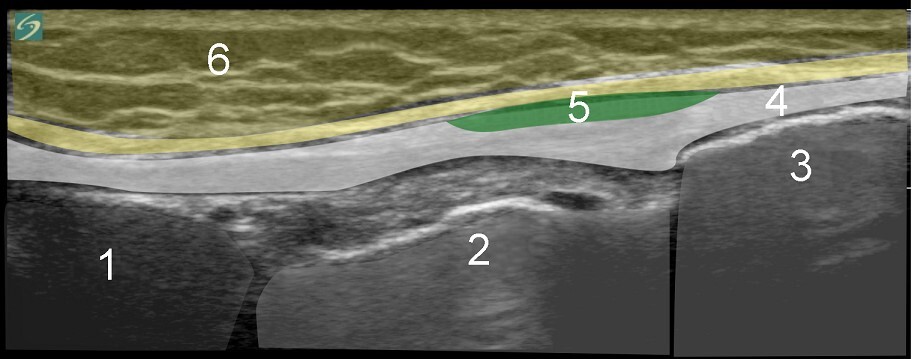

1. Lateral Meniscus

2. Tibia

3. Fibula

4. Distal Lateral Collateral Ligament (LCL)

5. Biceps Femoris

6. Subcutaneous Fat